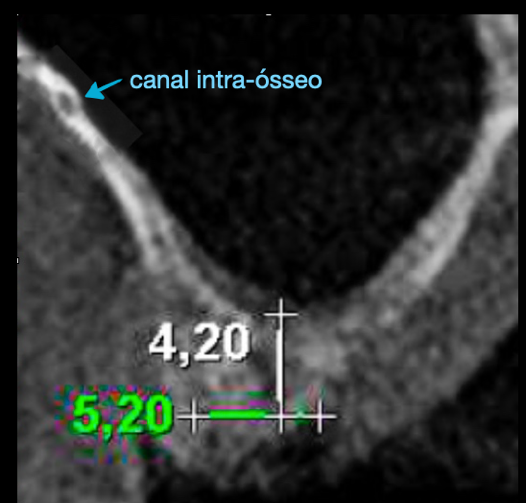

A irrigação da maxila é realizada por ramos de 2 principais vasos, a artéria alveolar superior posterior (AAPS) e a artéria infra-orbital (AIO), ramos da artéria maxilar 3,4. No estudo com tomografias de Khojastehpour et al 5 em 2016, eles encontraram anastomose na membrana entre as artérias AAPS e a AIO em 49.8% dos indivíduos, e do ponto de vista técnico nesssa condição, somente em casos de acidentes com rompimento da membrana sinusal poderia ocorrer hemorragias relevantes. Por outro lado, outros autores têm encontrado maior número de situações em que a AAPS se encontra intra-óssea, como nos estudos de Güncü et al 6 em 2011, e Ilgüi et al 7 em 2013, que observaram 68.2% e 71.1%, respectivamente. Quando a AAPS se encontra nessa última condição relatada, ocorre maior risco de dano vascular com hemorragia, especialmente se o canal vascular intra-ósseo for maior que 1 mm de espessura. Em média, alguns estudos têm demonstrado que a distância vertical do canal vascular da AAPS se apresenta próximo de 16 mm 5,7. Porém em casos de reabsorção do rebordo alveolar essa altura pode ser encontrada próximo de 11mm, segundo Rosano et al 4. A recomendação da tomografia como imagem de diagnóstico para identificação e mensuração da AAPS, pode estabelecer modificações estratégicas tanto na osteotomia, em relação ao desenho vertical e comprimento do implante, quanto na metodologia de instrumentação óssea. Podem ser usadas, por exemplo, ponteiras piezoelétricas sob irrigação para melhorar a visualização operatória e diminuir o risco de laceração vascular. As figuras de 1 a 12, demonstram caso clínico de técnica cirúrgica com osteotomia modificada, usando unidade piezo Mectron para remoção da parede lateral e preservar a AAPS, que foi diagnosticada em exame tomográfico durante a fase pré-operatória.